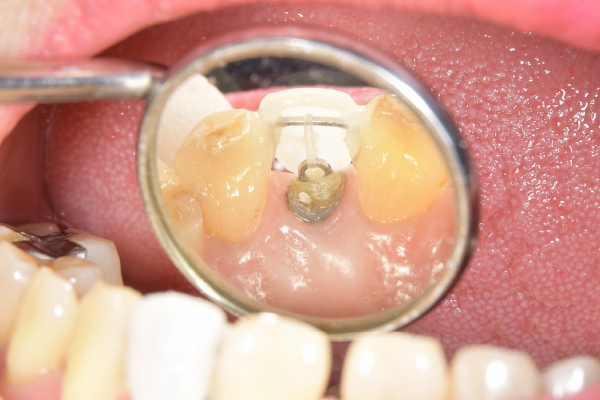

カリエスを取り除くと、遠心の歯質が歯肉縁下になりました。

MTM中。頬側には審美面の回復のために仮歯がついています。

歯からはフック、隣り合った歯にはワイヤーが渡してあります。そこにゴムをひっかけて歯を挺出させます。